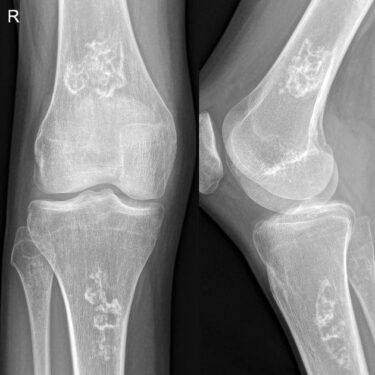

روشهای تشخیص

تشخیص صحیح نیازمند انجام بررسیهای دقیق است. رایجترین روشهای تشخیصی عبارتند از:

- عکسبرداری ساده (X-ray)

- دقیقترین روش برای تشخیص مراحل اولیه MRI می باشد.

- سیتی اسکن